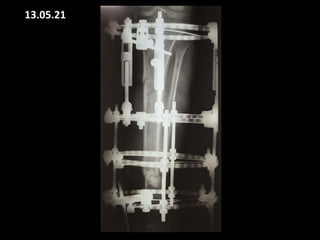

12.08.20

FOLLOW UP

25.09.21

17.11.20 25.11.20

25.01.21

18.03.2021

19.03.21

13.05.21

27.05.21